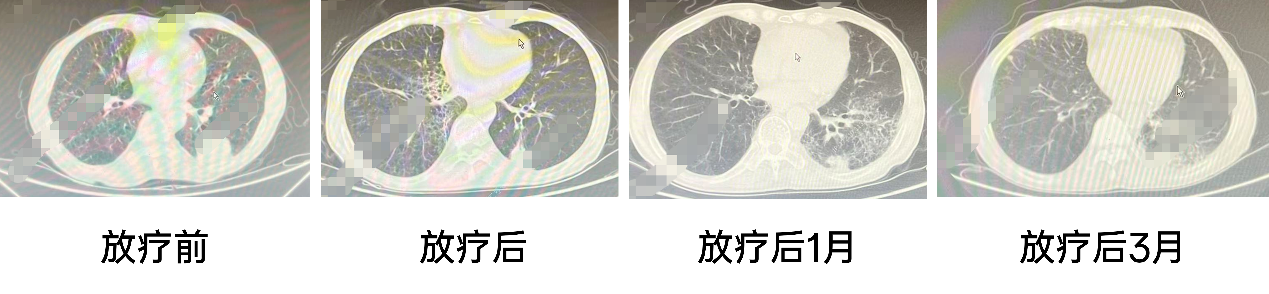

放疗前:2022-11-13 胸部增强CT:左肺下叶占位,考虑肿瘤性病变;肺气肿;右肺下叶结节;两肺下叶少许慢性炎症;局部冠脉钙化;右侧第4、5后肋陈旧性骨折。

放疗后:2023-01-27 胸部CT:左肺下叶CA较前变小;右肺下叶小结节较前相仿;肺气肿;右肺中叶、两肺下叶散在炎症,较前片新增;冠脉粥样硬化。

放疗后1月:2023-03-10 胸部CT:左肺下叶Ca较前大致相仿;双肺散在小结节、较前片大致相仿;肺气肿;两肺散在间质性改变(左肺尤著);冠脉钙化;右侧第4、5后肋陈旧性骨折。

放疗后3月:2023-05-02 胸部CT:左肺下叶Ca较前病灶略缩小,左肺下叶肺门淋巴结增大,伴支气管管腔变窄;右肺下叶小结节、较前片大致相仿;肺气肿;右肺中叶、双肺下叶间质性改变;冠脉钙化。右锁骨、右侧第4、5后肋陈旧性骨折改变。